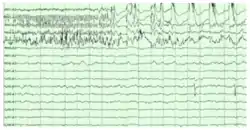

The hippocampus shows two major "modes" of activity, each associated with a distinct pattern of neural population activity and waves of electrical activity as measured by an electroencephalogram (EEG). These modes are named after the EEG patterns associated with them: theta and large irregular activity (LIA). The main characteristics described below are for the rat, which is the animal most extensively studied.[67]

The theta mode appears during states of active, alert behavior (especially locomotion), and also during REM (dreaming) sleep.[68] In the theta mode, the EEG is dominated by large regular waves with a frequency range of 6 to 9 Hz, and the main groups of hippocampal neurons (pyramidal cells and granule cells) show sparse population activity, which means that in any short time interval, the great majority of cells are silent, while the small remaining fraction fire at relatively high rates, up to 50 spikes in one second for the most active of them. An active cell typically stays active for half a second to a few seconds. As the rat behaves, the active cells fall silent and new cells become active, but the overall percentage of active cells remains more or less constant. In many situations, cell activity is determined largely by the spatial location of the animal, but other behavioral variables also clearly influence it.

The LIA mode appears during slow-wave (non-dreaming) sleep, and also during states of waking immobility such as resting or eating.[68] In the LIA mode, the EEG is dominated by sharp waves that are randomly timed large deflections of the EEG signal lasting for 25–50 milliseconds. Sharp waves are frequently generated in sets, with sets containing up to 5 or more individual sharp waves and lasting up to 500 ms. The spiking activity of neurons within the hippocampus is highly correlated with sharp wave activity. Most neurons decrease their firing rate between sharp waves; however, during a sharp wave, there is a dramatic increase of firing rate in up to 10% of the hippocampal population

Theta rhythm

Because of its densely packed neural layers, the hippocampus generates some of the largest EEG signals as theta waves of any brain structure, which generate the hippocampal theta rhythm.[70] In some situations the EEG is dominated by regular waves at 3 to 10 Hz, often continuing for many seconds. These reflect subthreshold membrane potentials and strongly modulate the spiking of hippocampal neurons and synchronise across the hippocampus in a travelling wave pattern.[71] The trisynaptic circuit is a relay of neurotransmission in the hippocampus that interacts with many brain regions. From rodent studies it has been proposed that the trisynaptic circuit generates the hippocampal theta rhythm.[72]

Theta rhythmicity is very obvious in rabbits and rodents and also clearly present in cats and dogs. Whether theta can be seen in primates is not yet clear.[73] In rats (the animals that have been the most extensively studied), theta is seen mainly in two conditions: first, when an animal is walking or in some other way actively interacting with its surroundings; second, during REM sleep.[74] The function of theta has not yet been convincingly explained although numerous theories have been proposed.[67] The most popular hypothesis has been to relate it to learning and memory. An example would be the phase with which theta rhythms, at the time of stimulation of a neuron, shape the effect of that stimulation upon its synapses. What is meant here is that theta rhythms may affect those aspects of learning and memory that are dependent upon synaptic plasticity.[75] It is well established that lesions of the medial septum—the central node of the theta system—cause severe disruptions of memory. However, the medial septum is more than just the controller of theta; it is also the main source of cholinergic projections to the hippocampus.[15] It has not been established that septal lesions exert their effects specifically by eliminating the theta rhythm.[76]

Sharp waves

During sleep or during resting when an animal is not engaged with its surroundings, the hippocampal EEG shows a pattern of irregular slow waves, somewhat larger in amplitude than theta waves. This pattern is occasionally interrupted by large surges called sharp waves.[77] These events are associated with bursts of spike activity lasting 50 to 100 milliseconds in pyramidal cells of CA3 and CA1. They are also associated with short-lived high-frequency EEG oscillations called "ripples", with frequencies in the range 150 to 200 Hz in rats, and together they are known as sharp waves and ripples. Sharp waves are most frequent during sleep when they occur at an average rate of around 1 per second (in rats) but in a very irregular temporal pattern. Sharp waves are less frequent during inactive waking states and are usually smaller. Sharp waves have also been observed in humans and monkeys. In macaques, sharp waves are robust but do not occur as frequently as in rats.[69]